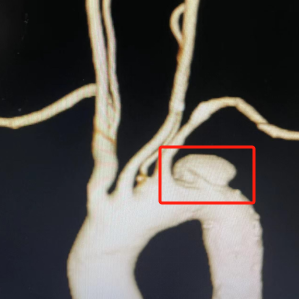

入院时患者血压高达200/100mmHg,胸腹部增强CT提示胸、腹主动脉多发壁间血肿,同时患者合并左侧髂总动脉瘤,内脏动脉和双下肢动脉斑块形成伴不同程度管腔的狭窄。

术中发现,患者左髂动脉瘤、腹主动脉多发溃疡、双下肢动脉狭窄在手术时带来了很大的挑战。放射介入科团队在张余副主任的带领下,小心通过导丝、输送支架,避免了手术对其他血管的损伤。